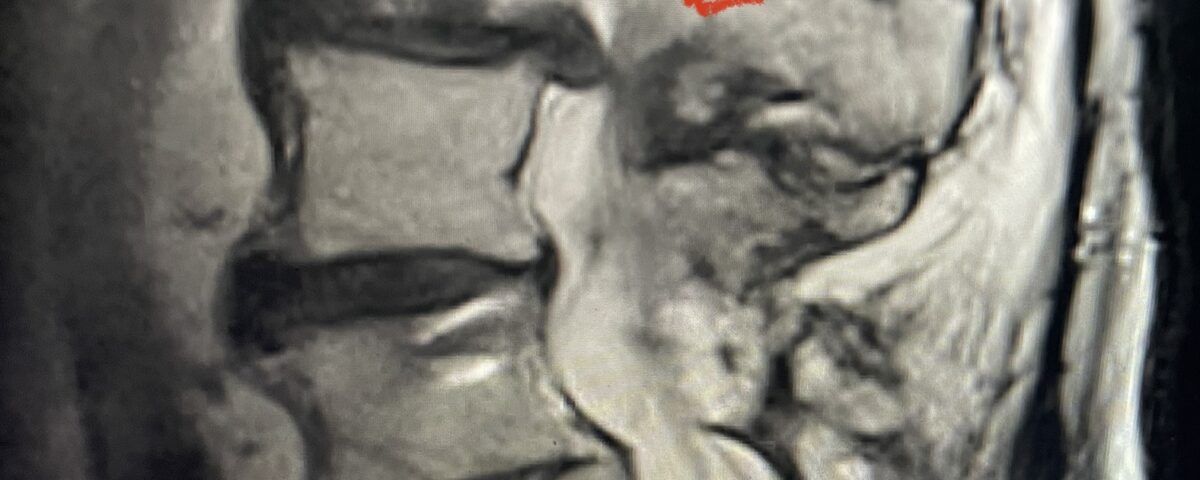

In patients who have lumbar spinal stenosis and significant cardio/pulmonary conditions, surgery is the last resort. However, some patients with these conditions may fail all means of conservative management where surgery becomes their only option for relief. In those patients, one should strive to do the least complex surgery that is necessary to get the job done for them. In this case study, we are confronted with a new problem in a 78 year-old male patient that was in poor medical condition who had had two prior lumbar laminectomies with resultant fusion and instrumentation from L4-S1. There was now retrolisthesis of L2-3 with severe stenosis (Fig.1)

Fig 1a: Sagittal T2 weighted lumbar MRI demonstrating severe L2-3 stenosis (red arrow)